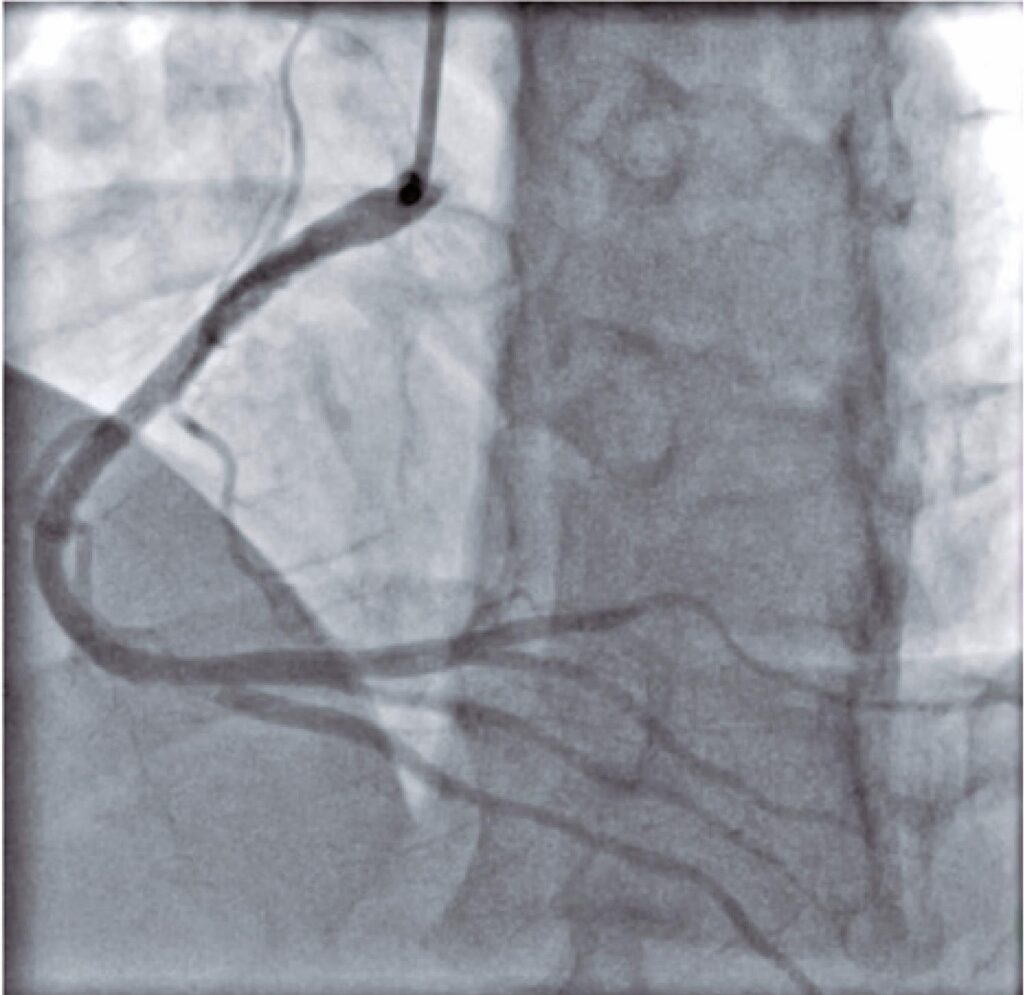

Trombose coronariana em paciente jovem sem comorbidades após infecção pela COVID-19

A COVID-19 emergiu como uma infecção viral causadora da síndrome respiratória aguda grave, tomando proporções globais no ano de 2020, com impactos significativos na saúde pública. A maior severidade da infecção em portadores de doenças cardiovasculares tem tornado o cenário alarmante, com mortalidade até quatro vezes maior em relação à população geral. Como provável contribuinte, o estado inflamatório pró-trombótico vem sendo alvo de discussão no meio científico, ainda sem terapêuticas consolidadas a curto e longo prazo. Descrevemos o caso de um paciente jovem, sem fatores de risco cardiovasculares, com infarto agudo do miocárdio com supradesnivelamento do segmento ST causado por trombose coronariana no período tardio pós-infecção pela COVID-19, revisando as mais recentes recomendações para seu tratamento.